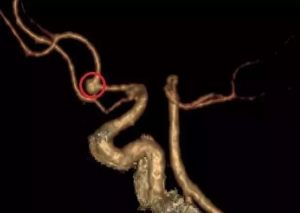

然而,夫妻俩的体检结果却让他们深感诧异。结果显示,妻子除了有肠息肉外,基本没有大问题,而张先生不仅有肠息肉,还查出脑部有颗“隐形炸弹”——脑动脉瘤,大小为5.2*4.5mm。

张先生的影像图片 红色区域为动脉瘤